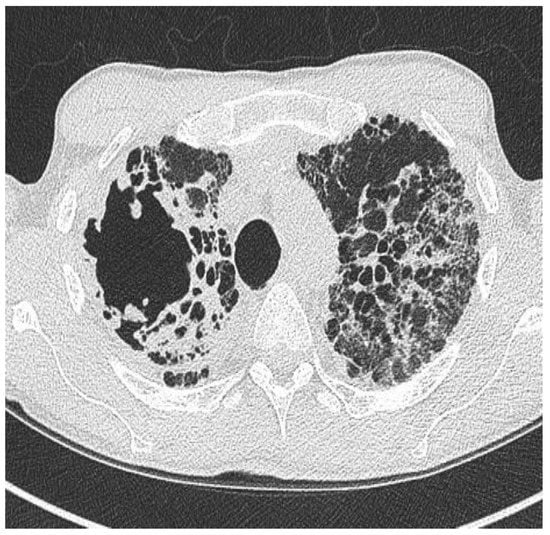

2.1. Clinical Phenotype by Radiology

- Juliusson, G.; Gudmundsson, G. Diagnostic imaging in adult non-cystic fibrosis bronchiectasis. Breathe 2019, 15, 190–197. [Google Scholar] [CrossRef]